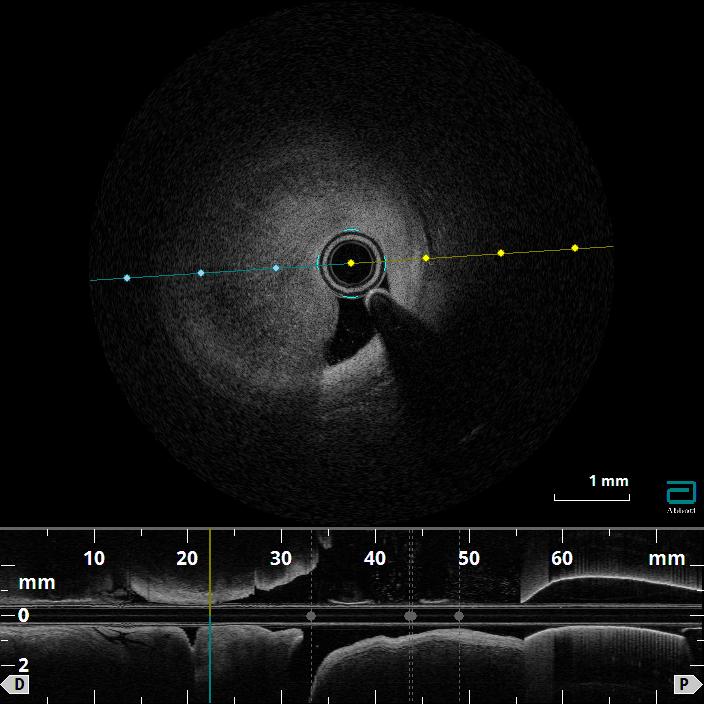

Relevant Catheterization Findings

Coronary angiography confirmed a hemodynamically significant stenosis in the mid-LAD, consistent with CCTA. OFDI revealed a high-intensity, heterogeneous signal with layered structure and microchannel formation, features suggestive of an organized thrombus rather than a lipid-rich atherosclerotic plaque. This morphology was considered to be associated with a low risk of plaque restenosis and favorable balloon response, making a stent-free strategy a reasonable therapeutic option.

The target mid-LAD lesion was initially treated with excimer laser coronary angioplasty (ELCA) to ablate thrombotic tissue and facilitate subsequent vessel preparation. Following laser irradiation, prolonged low-pressure balloon dilatation was performed to optimize lesion modification and achieve adequate luminal expansion. Subsequently, a paclitaxel-coated drug-coated balloon (DCB) was applied at the treated segment to deliver antiproliferative therapy without stent implantation. Final angiography showed satisfactory luminal gain with TIMI 3 flow, and no evidence of vessel recoil or major dissection. Post-procedural OFDI confirmed a well-expanded lumen with smooth vessel surface, and no significant residual thrombus or flow-limiting dissection. The patient was discharged on dual antiplatelet therapy for 3 months. At 2-year follow-up, CCTA demonstrated sustained vessel patency without restenosis, supporting the long-term durability of this stentless ELCA+DCB strategy.